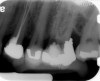

Fig 9 Preoperative radiographs showing mesial perforation.

Figure 9

Fig 10. Preoperative radiographs showing mesial perforation.

Figure 10

Clinical procedure: Once a perforation occurs, the extent of the perforation must be assessed. If there is an adjacent bony defect, the bony defect should first be filled with an osteoconductive or osteoinductive material. This can be done with a bone graft, calcium sulfate, or collagen/gelatin sponge. The dentinal portion of the tooth that has been perforated is then restored with MTA (Figure 9 through Figure 14).

Perforations are generally the result of iatrogenic conditions in which a communication between the pulp canal and the periradicular tissue occurs during either access preparation or canal shaping procedures. Perforations can also happen in cases of internal root resorption, where the entire thickness of the root becomes affected by the resorptive process. Because of its excellent sealing ability and biocompatibility, MTA has been used to repair root perforations with predictable results.29,30